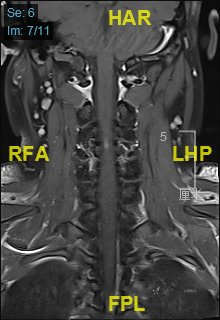

颈部磁共振平扫:

颈部磁共振平扫后增强: